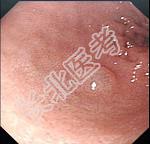

- 单项选择题男,70岁, 剑突下疼痛伴进行性咽下困难1个月,消瘦、乏力明显, 粪隐血持续阳性,内镜及影像检查如下图, 诊断为 ( )

D、贲门癌